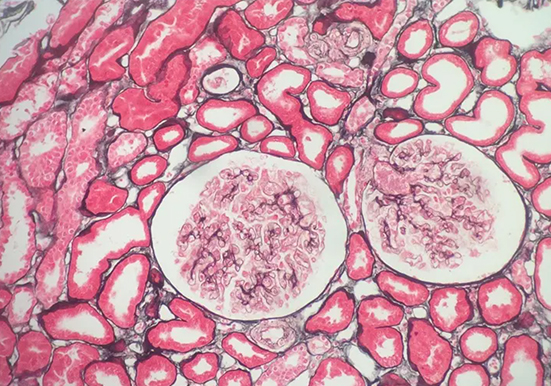

刚果红染色

刚果红染色是一种常用的生物染色方法,以下是关于它的详细介绍:

染料性质:刚果红是一种经典的酸性染料,化学式为 C32H22N6Na2O6S2,是一种棕红色粉末,能溶于水和乙醇。

染色原理:主要依赖于其与蛋白质及其他生物大分子的亲和性,通过静电吸引、氢键等作用力与样品中的不同组分发生相互作用,使样品呈现出特定的颜色。